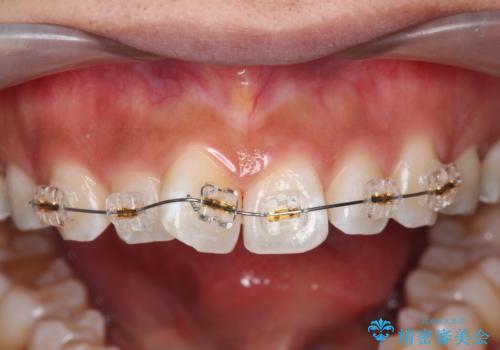

- 矯正装置

- インビザライン

マウスピース矯正を始める前に、ねじれを取るのが短期間で済む部分ワイヤー小矯正を行うことで、全体的な治療期間を短くする治療計画を実行していきます。

前歯のねじれはマウスピース矯正の苦手な動きになり、治療期間が長くなる原因になりやすいです。